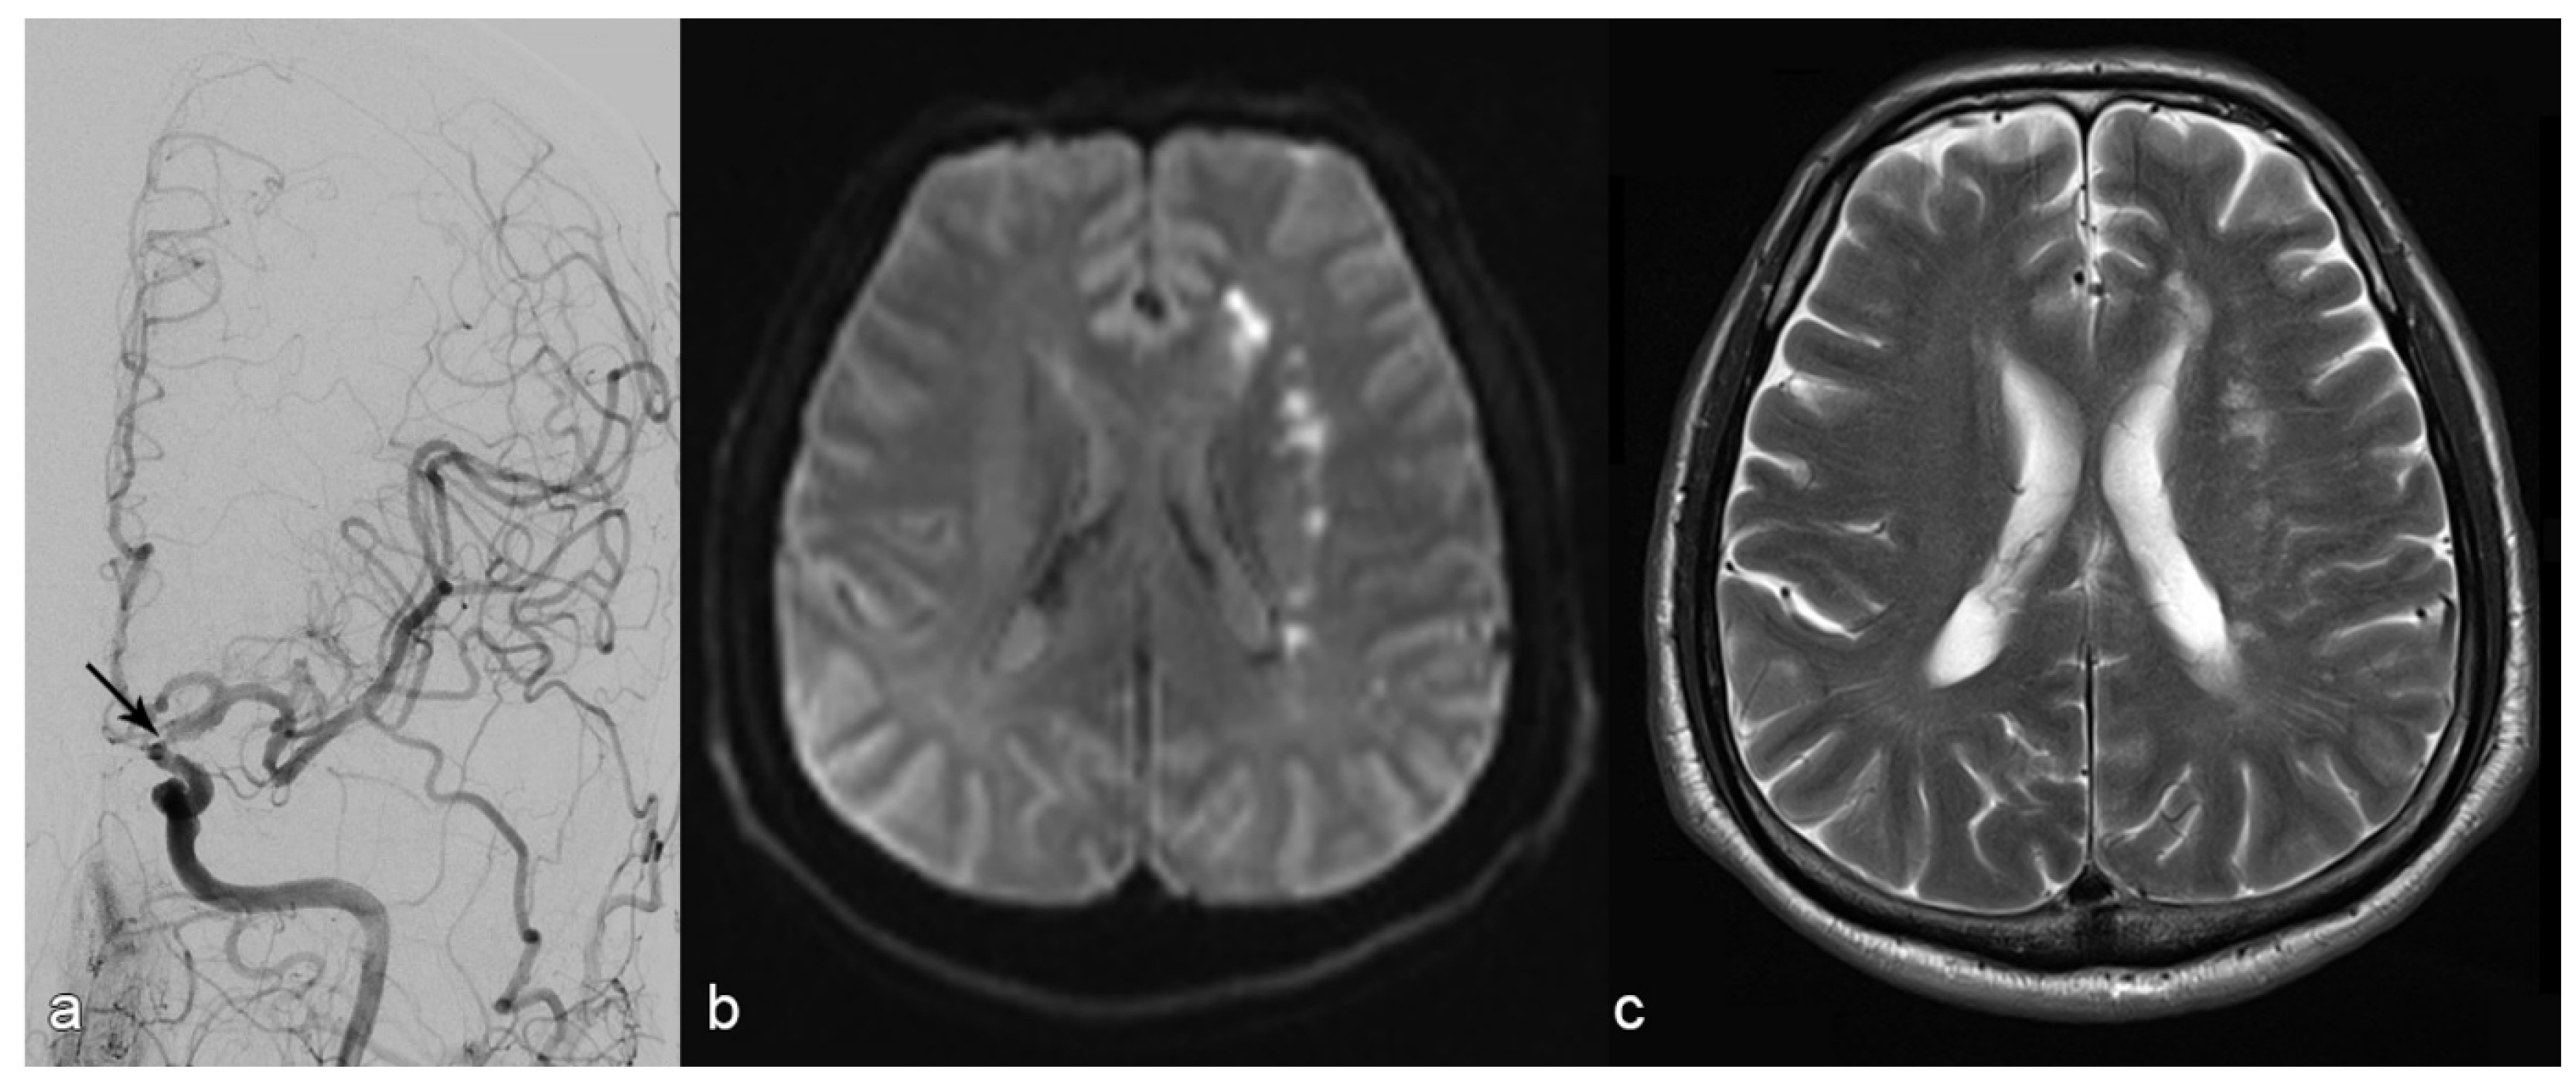

- Intracranial dissections with compromised side branch patency occurred in two out of 32 patients. Both cases were in the vertebrobasilar circulation and occurred after balloon angioplasty. In one of these two cases, there was subsequent in-stent thrombosis, which was fatal. In the other case, there were embolic and perforator infarction which led to worsening of the neurologic symptoms.

- Acute and subacute stent thrombosis were observed in two cases, both of which occurred in the vertebrobasilar circulation and were symptomatic: one of these two patients had progressive infarction, which led to neurological worsening (mRS=5); the other had stent-thrombosis after dissection, which was fatal (mentioned previously).